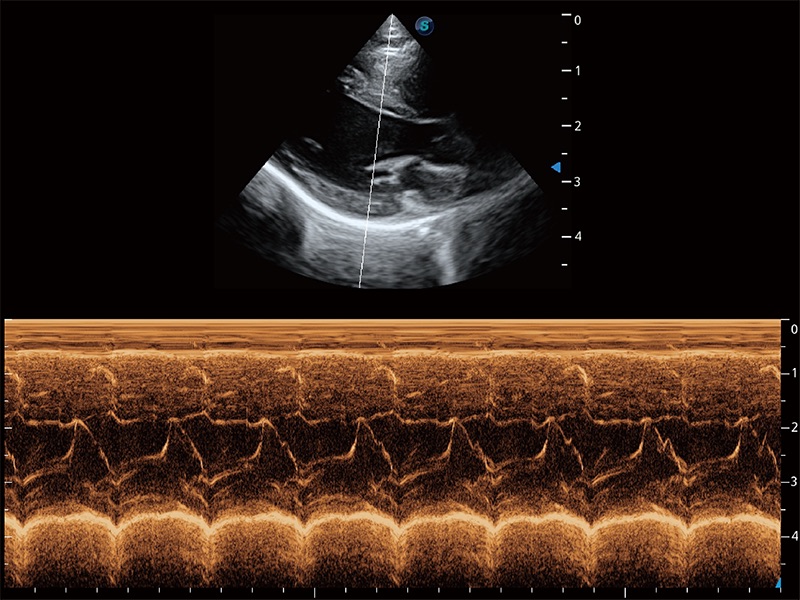

通过360度任意调节3条M型取样线,在同一心动周期上观察心脏不同位置的运动曲线,得到准确的心功能测量数据,有效评估心肌运动及左心室功能。

能够基于左心室壁追踪和辛普森法,自动计算射血分数,支持多个可移动点描迹,与手动测量相比,极大节省了动物医生的时间和精力。